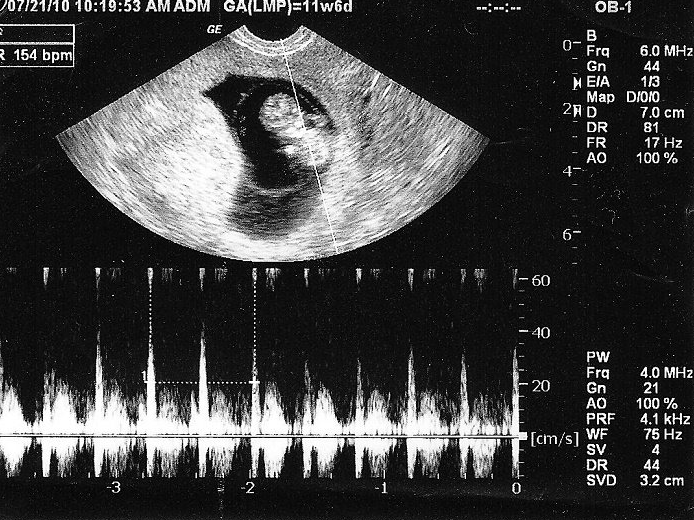

Ngoài quan tâm thai mấy tuần thì siêu âm được, mẹ còn muốn biết thời điểm nào thích hợp để siêu âm tim thai lần đầu.

Mẹ lưu ý rằng thời điểm siêu âm tim thai lần đầu tốt nhất thường được thực hiện ở tuần thứ 6 - 8 của thai kỳ.

Tuy từ tuần thứ 5 tim thai đã hình thành và có nhịp đập nhưng tùy cơ địa và chu kỳ kinh nguyệt của mỗi mẹ bầu nên thời điểm tim thai hình thành, phát triển sẽ khác nhau.

Có vài trường hợp cá biệt tim thai xuất hiện ở tuần thứ 10 của thai kỳ. Vì thế mẹ cũng không cần phải lo lắng nếu siêu âm ở tuần thứ 6 chưa thấy tim thai. Hãy thăm khám và siêu âm lại lần nữa theo chỉ định của bác sĩ.

Siêu âm tim thai được tiến hành tốt nhất từ tuần thứ 18 đến tuần 22 của thai kỳ. Đây là giai đoạn quan trọng nhất để thăm khám, siêu âm, xét nghiệm, kiểm tra dị tật thai nhi. Nhưng bác sĩ vẫn có thể chỉ định mẹ bầu siêu âm tim từ tuần thứ 20 đến tuần thứ 22.

Trong đó, siêu âm tim thai tuần thứ 22 có thể cho kết quả chính xác, nhờ đó bác sĩ sẽ đưa ra sự tư vấn tốt nhất cho mẹ về tình trạng của thai nhi.